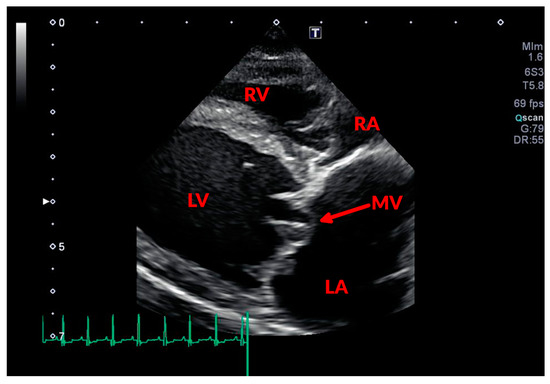

3.1. Conventional Echocardiography

3.1.1. Assessing MR Severity

3.1.2. Assessing Cardiac Remodeling